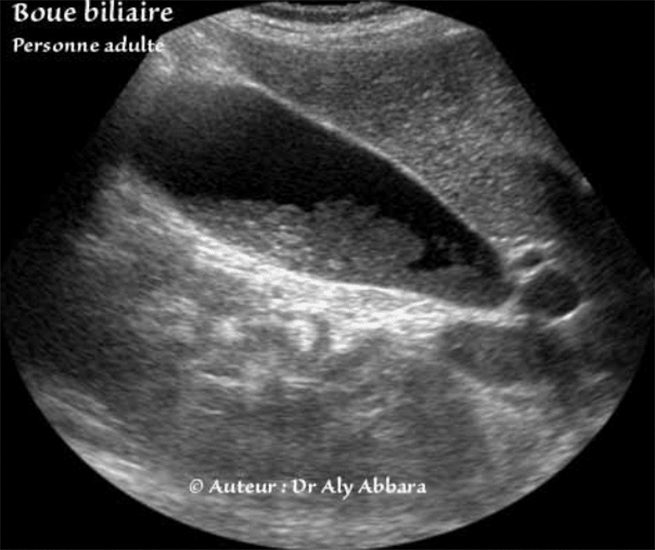

Vésicule biliaire contenant de la boue biliaire (Femme de 33 ans : quatrième jour du post-partum). La vésicule biliaire en coupe longitudinale et transversale. On remarque l'absence d'atténuation distale acoustique (cône d'ombre) derrière cette formation nitra-vésiculaire. A comparer à l'aspect de la boue biliaire chez un fœtus |